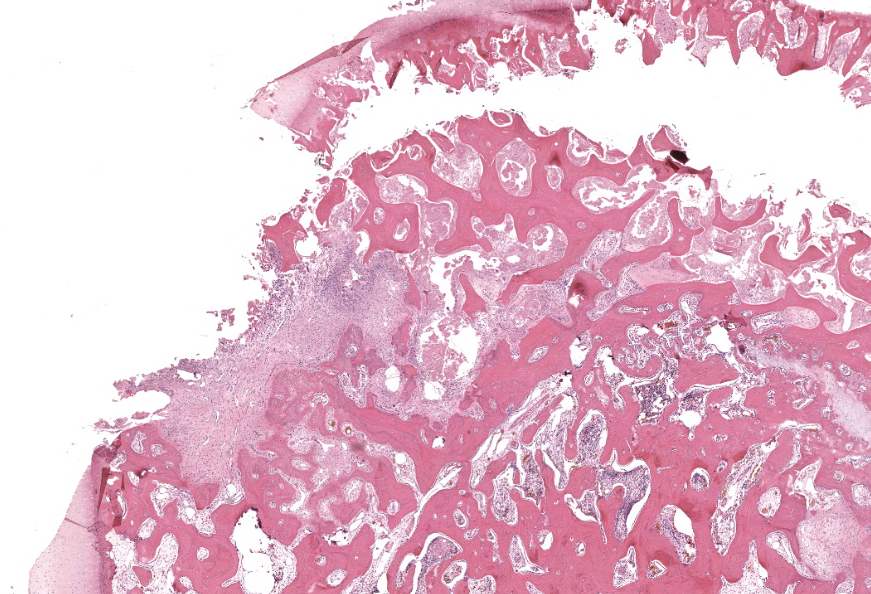

Femoral head: Affecting approximately 30-50% of the epiphysis from the subchondral aspect of the articular cartilage to the physis, there is a focally extensive area of osteonecrosis characterized by bony trabeculae which are irregular and brightly eosinophilic with loss of differential staining. There is loss of both osteocytes within lacunae and osteoblasts lining trabeculae in this region. Along the margins of the necrotic area, multiple bone trabeculae are fragmented and/or have scalloped margins with osteoclasts in Howship’s lacunae (osteolysis). The intertrabecular spaces within and at the periphery of the necrotic area contain variably amounts of amorphous eosinophilic matrix (fibrin), occasional neutrophils and macrophages and/or loosely arranged myxomatous to collagenous matrix with variable numbers of plump spindle cells and capillaries (fibroplasia). Occasionally, there are also finer, irregular trabeculae of paler staining or partially mineralized bone (woven bone). Adjacent viable trabeculae are lined by numerous active osteoblasts (remodeling) and are sometimes laced with wavy basophilic lines (resting / resorption lines). The articular cartilage is fragmented (likely artefact).Contributor's Morphologic Diagnoses:

Osteonecrosis, focally extensive, chronic with fibroplasia and bone remodeling; femoral head.Contributor's Comment: